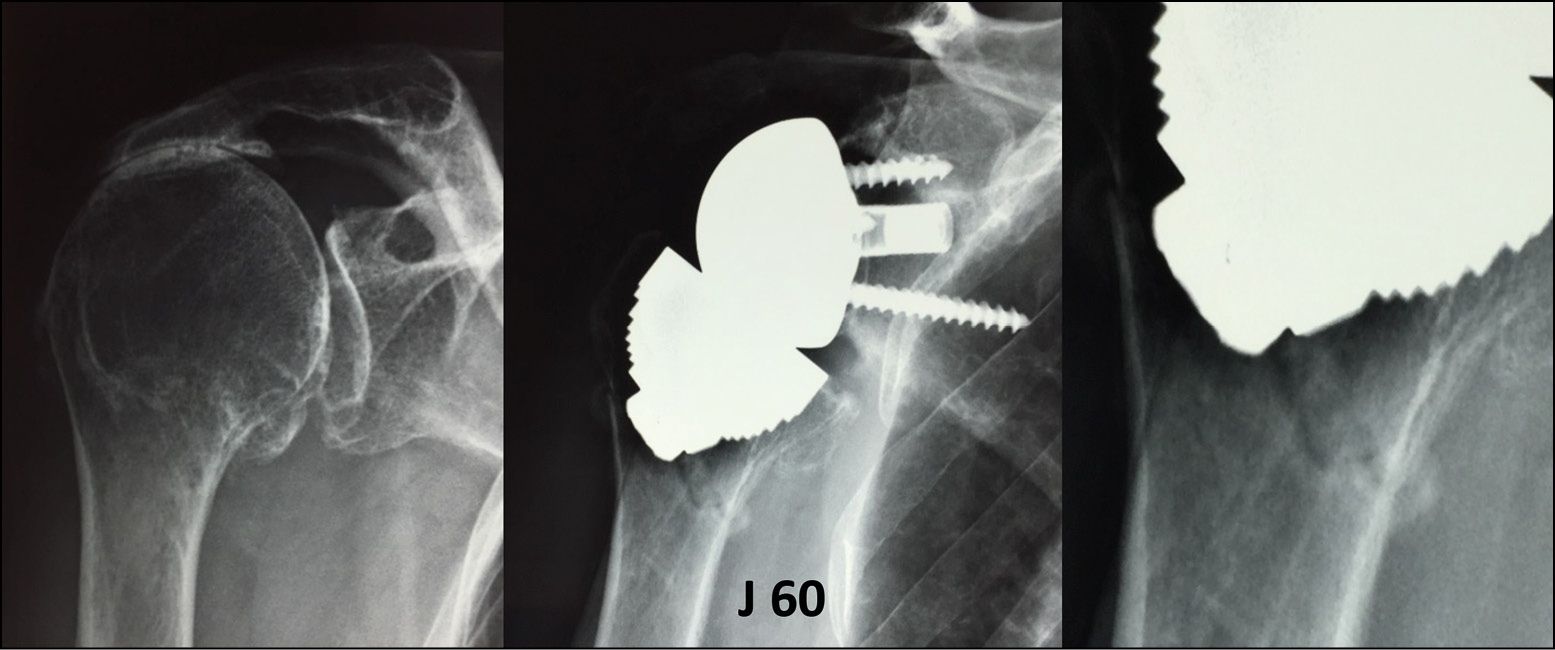

Mediocre bone quality caused by long-term steroid therapy, osteoporosis and polyarthritis are contraindications to the use of a stemless design due to the risk of loosening or stress fractures (Fig. 22). Age is not in itself a limiting factor, provided there is sufficient quality bone stock.[6] Keith M Baumgarten. L’arthroplastie totale de l’épaule sans tige est-elle indiquée chez les patients agés ? JSES 2023. 32(2) 260-268

Insufficient epiphysometaphyseal bone stock is a limitation for stemless. The bone walls surrounding the humeral implant must be solid and encompassing. When preparing the glenoid cavity, the posterior spacer used to push back the humeral head can sometimes damage the anterior wall of the humeral epiphysis, creating the need for a stem.